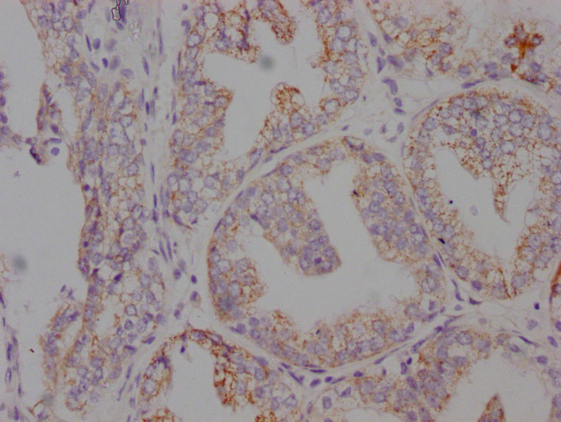

IHC image of CSB-MA546610 diluted at 1:100 and staining in paraffin-embedded human prostate cancer performed on a Leica BondTM system. After dewaxing and hydration, antigen retrieval was mediated by high pressure in a citrate buffer (pH 6.0). Section was blocked with 10% normal goat serum 30min at RT. Then primary antibody (1% BSA) was incubated at 4°C overnight. The primary is detected by a Goat anti-mouse IgG polymer labeled by HRP and visualized using 0.05% DAB.